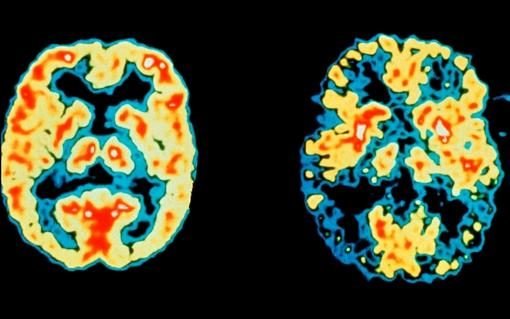

به گزارش ایسنا، بررسی محققان آمریکایی نشان میدهد: ۱۰ سال پیش از بروز هر گونه علائم زوال عقلی مرتبط با بیماری آلزایمر، سطح فزایندهای از پلاکهای آمیلوئید در مغز تشکیل میشود که میتواند از اولین مراحل ابتلا به این بیماری عنوان شود.

وجود این پلاکها نشان میدهد که تخریب مغز ناشی از بیماری آلزایمر میتواند سالها پیش از شناسایی علائم آن شروع شود. همچنین میتوان درمان بیماری را زودتر آغاز کرد.